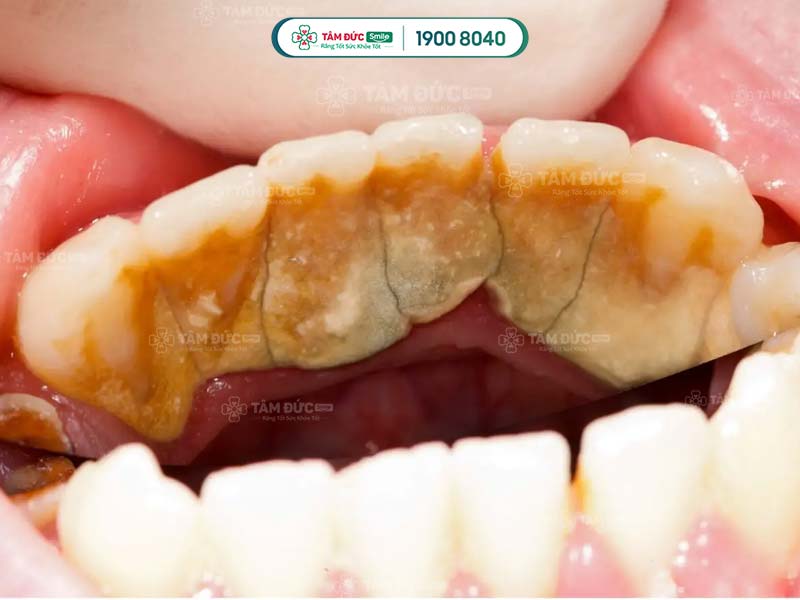

• Phát hiện có nhiều cao răng và mảng bám ở thân răng hoặc dưới nướu.

các trường hợp nên cạo cao răng